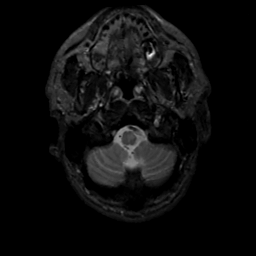

MR Study #3, February 24, 1991 -- Slice #4

[Home][Help][Clinical][Tour 1][Tour 2] Slice 4